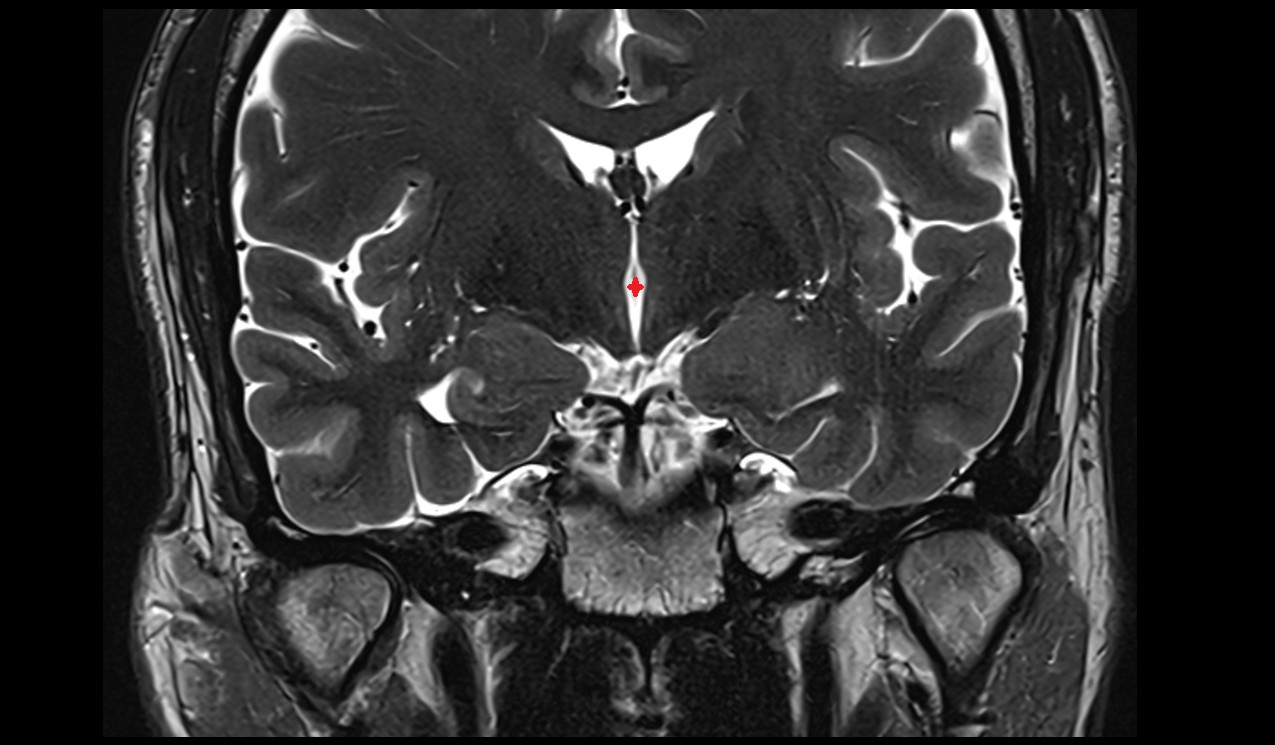

- Interventricular foramen

- Third ventricle